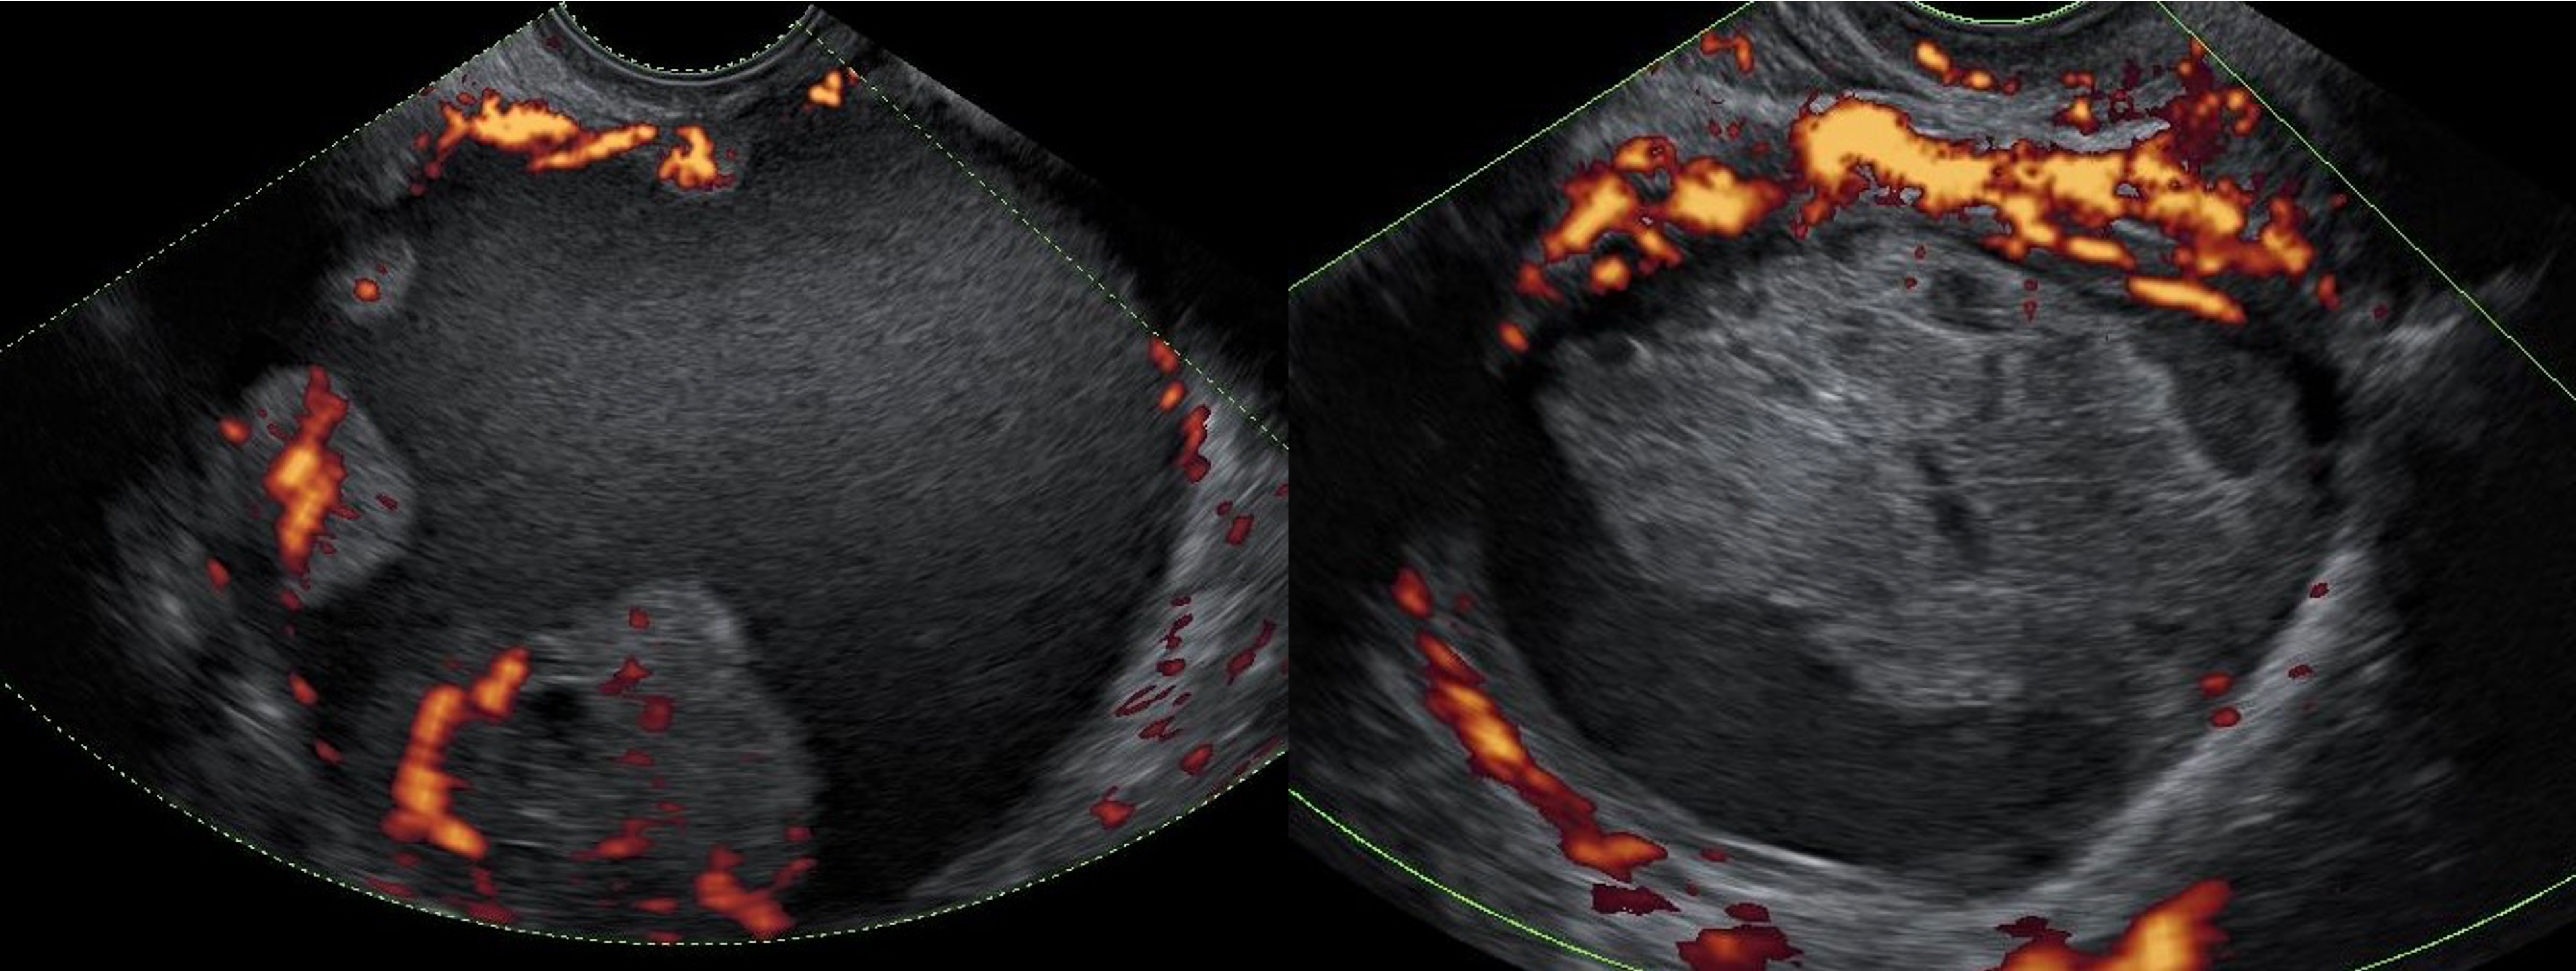

Ultrasound images of two ovarian lesions—an ovarian cancer (left) and a benign functional lesion (right)—with power Doppler visualizing their vascular activity.